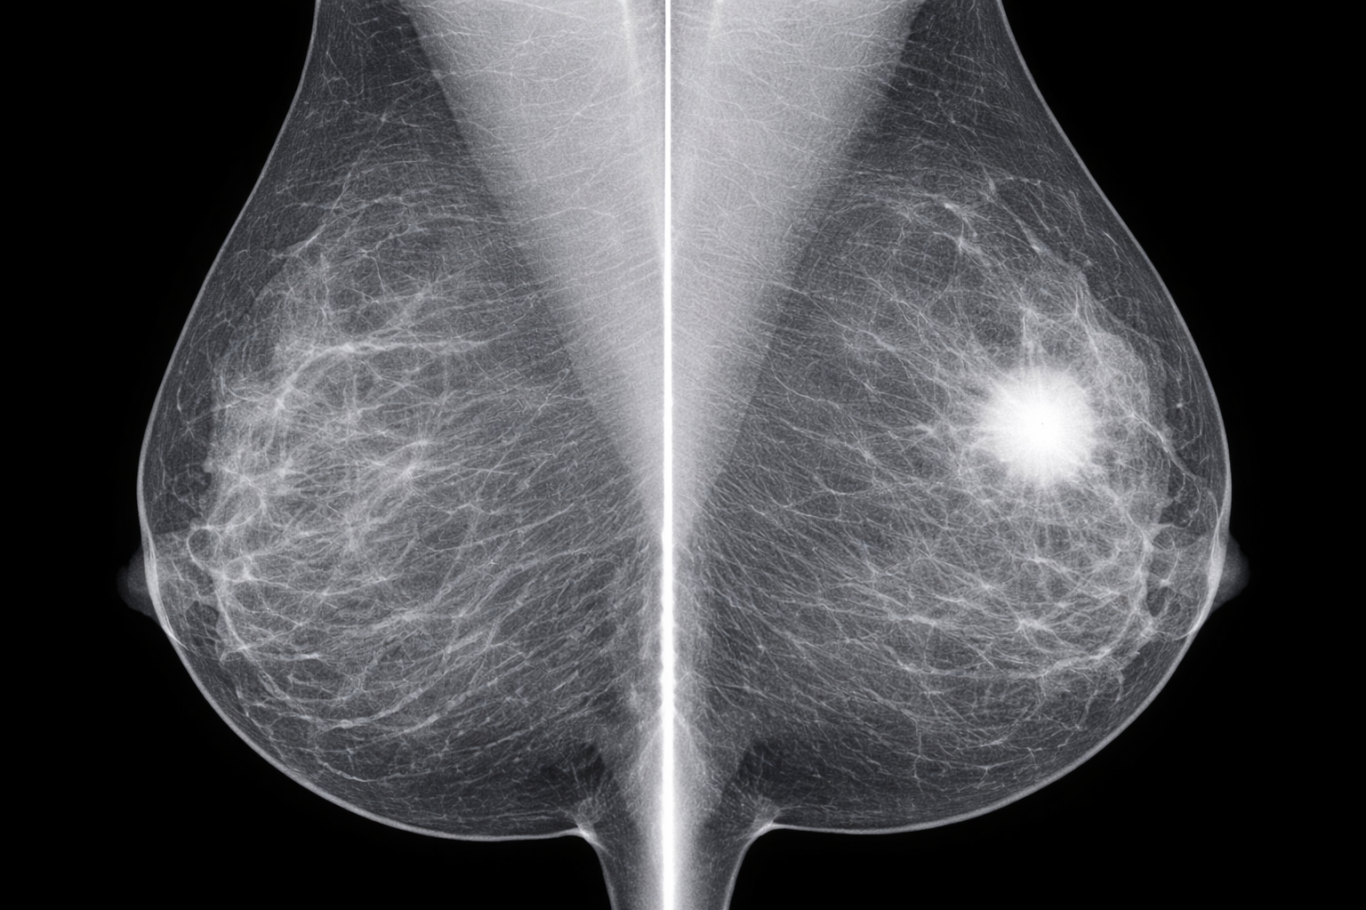

Mammographie

La mammographie est un examen d’imagerie médicale qui utilise des rayons X à faible dose pour analyser les tissus du sein. Elle permet de détecter précocement des anomalies mammaires, notamment les cancers du sein, parfois avant l’apparition de symptômes. Cet examen est utilisé à la fois dans le cadre du dépistage et du diagnostic.